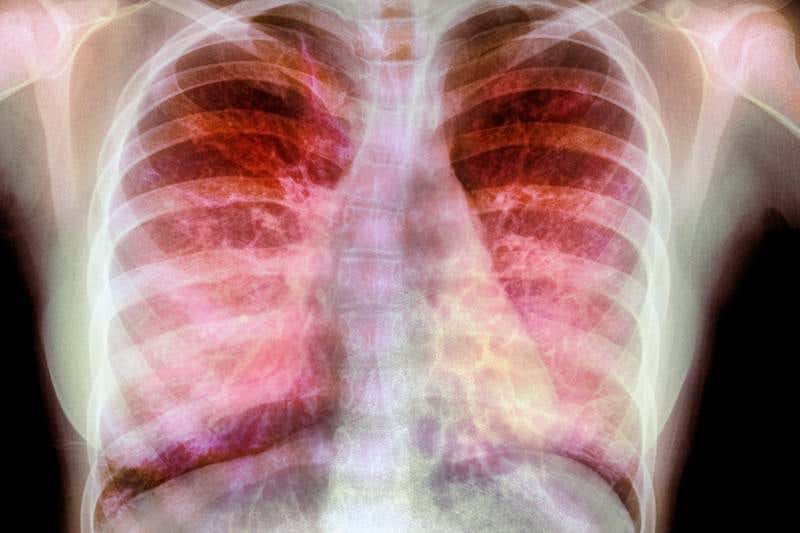

The lungs are well defended by the immune system (Image: Guy Viner/SPL)

Cystic fibrosis is one of the most common genetic diseases, affecting about 70,000 people worldwide. Mutations in a single gene, CFTR, clog the lungs with thick mucus. Despite gruelling physiotherapy to clear it, lung function steadily gets worse, lowering life expectancy to around 40 years.

Researchers have long tried to put healthy copies of CFTR into damaged lung cells, but the immune system’s defences scuppered all efforts. A team of 80 scientists and clinicians now seem to have cracked this by smuggling in the gene inside fatty bubbles called liposomes.